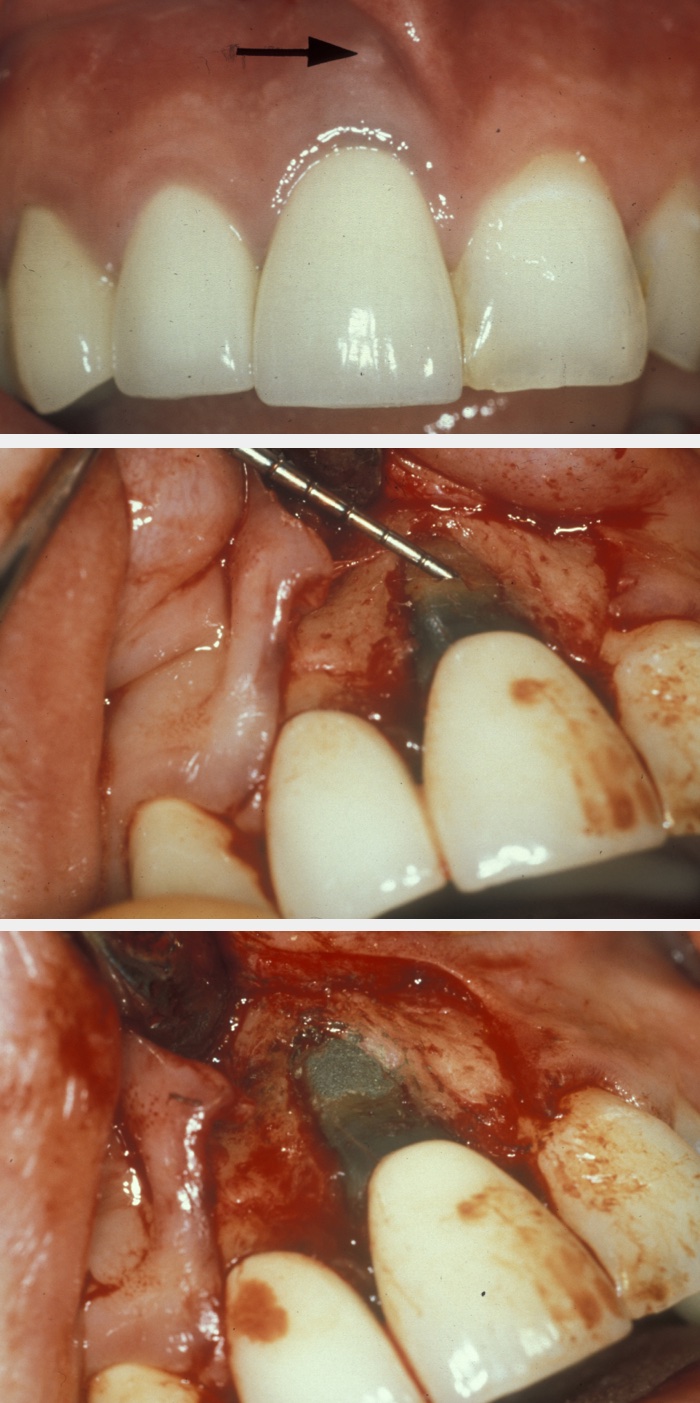

Perforation repair becomes necessary to deal with root perforations caused by broken endodontic instruments or damage by posts, and resorption cavities. If the prognosis of the tooth is acceptable, surgical access is gained to the site of the perforation, the area is prepared and then filled with, for example, mineral trioxide aggregate. Figure 1 illustrates an example; the apparent over-bevelling is a consequence of this being a perforation repair and not a conventional apicectomy.

Figure 1: Top: labial swelling (arrow) related to a post perforation at the upper right incisor (UR1); middle: flap raised and curettage of the surgical area effected, a periodontal probe was used to identify the defect; bottom: defect repaired with mineral trioxide aggregate to re-establish the correct root contour.